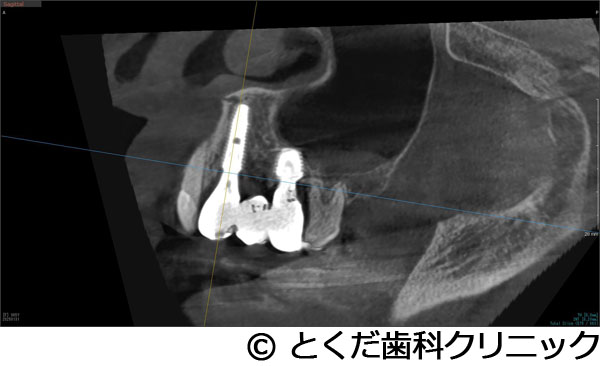

¡Ú¾ÉÎã2¡Û¤«¤Ê¤ê¾å³Ü¹ü¤¬¤Ê¤¤¡Ê¾å³Ü´û¸¹ü1.5¡Á2mm¤·¤«¤Ê¤¤¡Ë¥±¡¼¥¹¤Ç¡¢¤ï¤º¤«2¥õ·îȾ¤Ç¼£ÎŤò½ª¤¨¤¿¥±¡¼¥¹

- ¤«¤Ê¤ê¾å³Ü¹ü¤¬¤Ê¤¤¡Ê¾å³Ü´û¸¹ü1.5¡Á2mm¤·¤«¤Ê¤¤¡Ë¥±¡¼¥¹¤Ç¡¢¤ï¤º¤«2¥õ·îȾ¤Ç¼£ÎŤò½ª¤¨¤¿¥±¡¼¥¹

±¦¾å6È֤λõ¤¬»õ¼þÉ¤Τ¿¤á¡¢¼«Á³¤ËÈ´¤±¤Æ¤·¤Þ¤Ã¤¿¡£

¼£ÎÅÊýË¡

»õ¼þɤˤè¤ê¡¢±¦Â¦6È֤ξå³Ü¹ü¤¬µÛ¼ý¤·¤Æ¡¢1.5¡Á2mmÄøÅ٤ιü¤·¤«»Ä¤Ã¤Æ¤¤¤Ê¤«¤Ã¤¿¤¿¤á¡¢½¾Íè¤Ê¤éÂ礤ʿ¯½±¤È1ǯ°Ê¾å¤Î¼£ÎÅ´ü´Ö¤¬¤«¤«¤ë¥µ¥¤¥Ê¥¹¥ê¥Õ¥È¤¬É¬ÍפǤ¢¤Ã¤¿¤¬¡¢´µ¼ÔÍͤؤλþ´ÖŪ¡¢ÆùÂÎŪ¡¢¶âÁ¬ÅªÉéô¤¬Â礤¯¤Ê¤ë¤³¤È¤ò¹Íθ¤·¤Æ¡¢º£²ó¤Ï¡¢¥¨¥¯¥¹¥È¥é¥ï¥¤¥É¥·¥ç¡¼¥È¥¤¥ó¥×¥é¥ó¥È¤È¥Ç¥ó¥µ¡¼¥Ð¡¼¤ò»ÈÍѤ·¤¿¥°¥é¥Õ¥È¥ì¥¹¥µ¥¤¥Ê¥¹¥ê¥Õ¥È¤òÁªÂò¤·¤Æ¡¢¤ï¤º¤«¡¢2.5¥õ·î¤Ç¾åÉô¥¸¥ë¥³¥Ë¥¢¤ÎºÇ½ªÊäÄÖʪ¤òÁõÃ夷¤Æ¼£ÎŤò½ª¤¨¤Æ¤¤¤Þ¤¹¡£